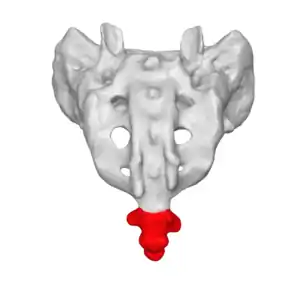

![]() | |

| The location of the coccyx (in red) at the lower aspect of the sacrum of the pelvis | |